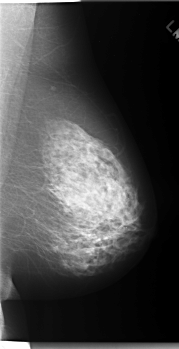

C_0085_1.LEFT_MLO

LEFT_MLO LINES 5928 PIXELS_PER_LINE 3040 BITS_PER_PIXEL 12 RESOLUTION 50 NON_OVERLAY